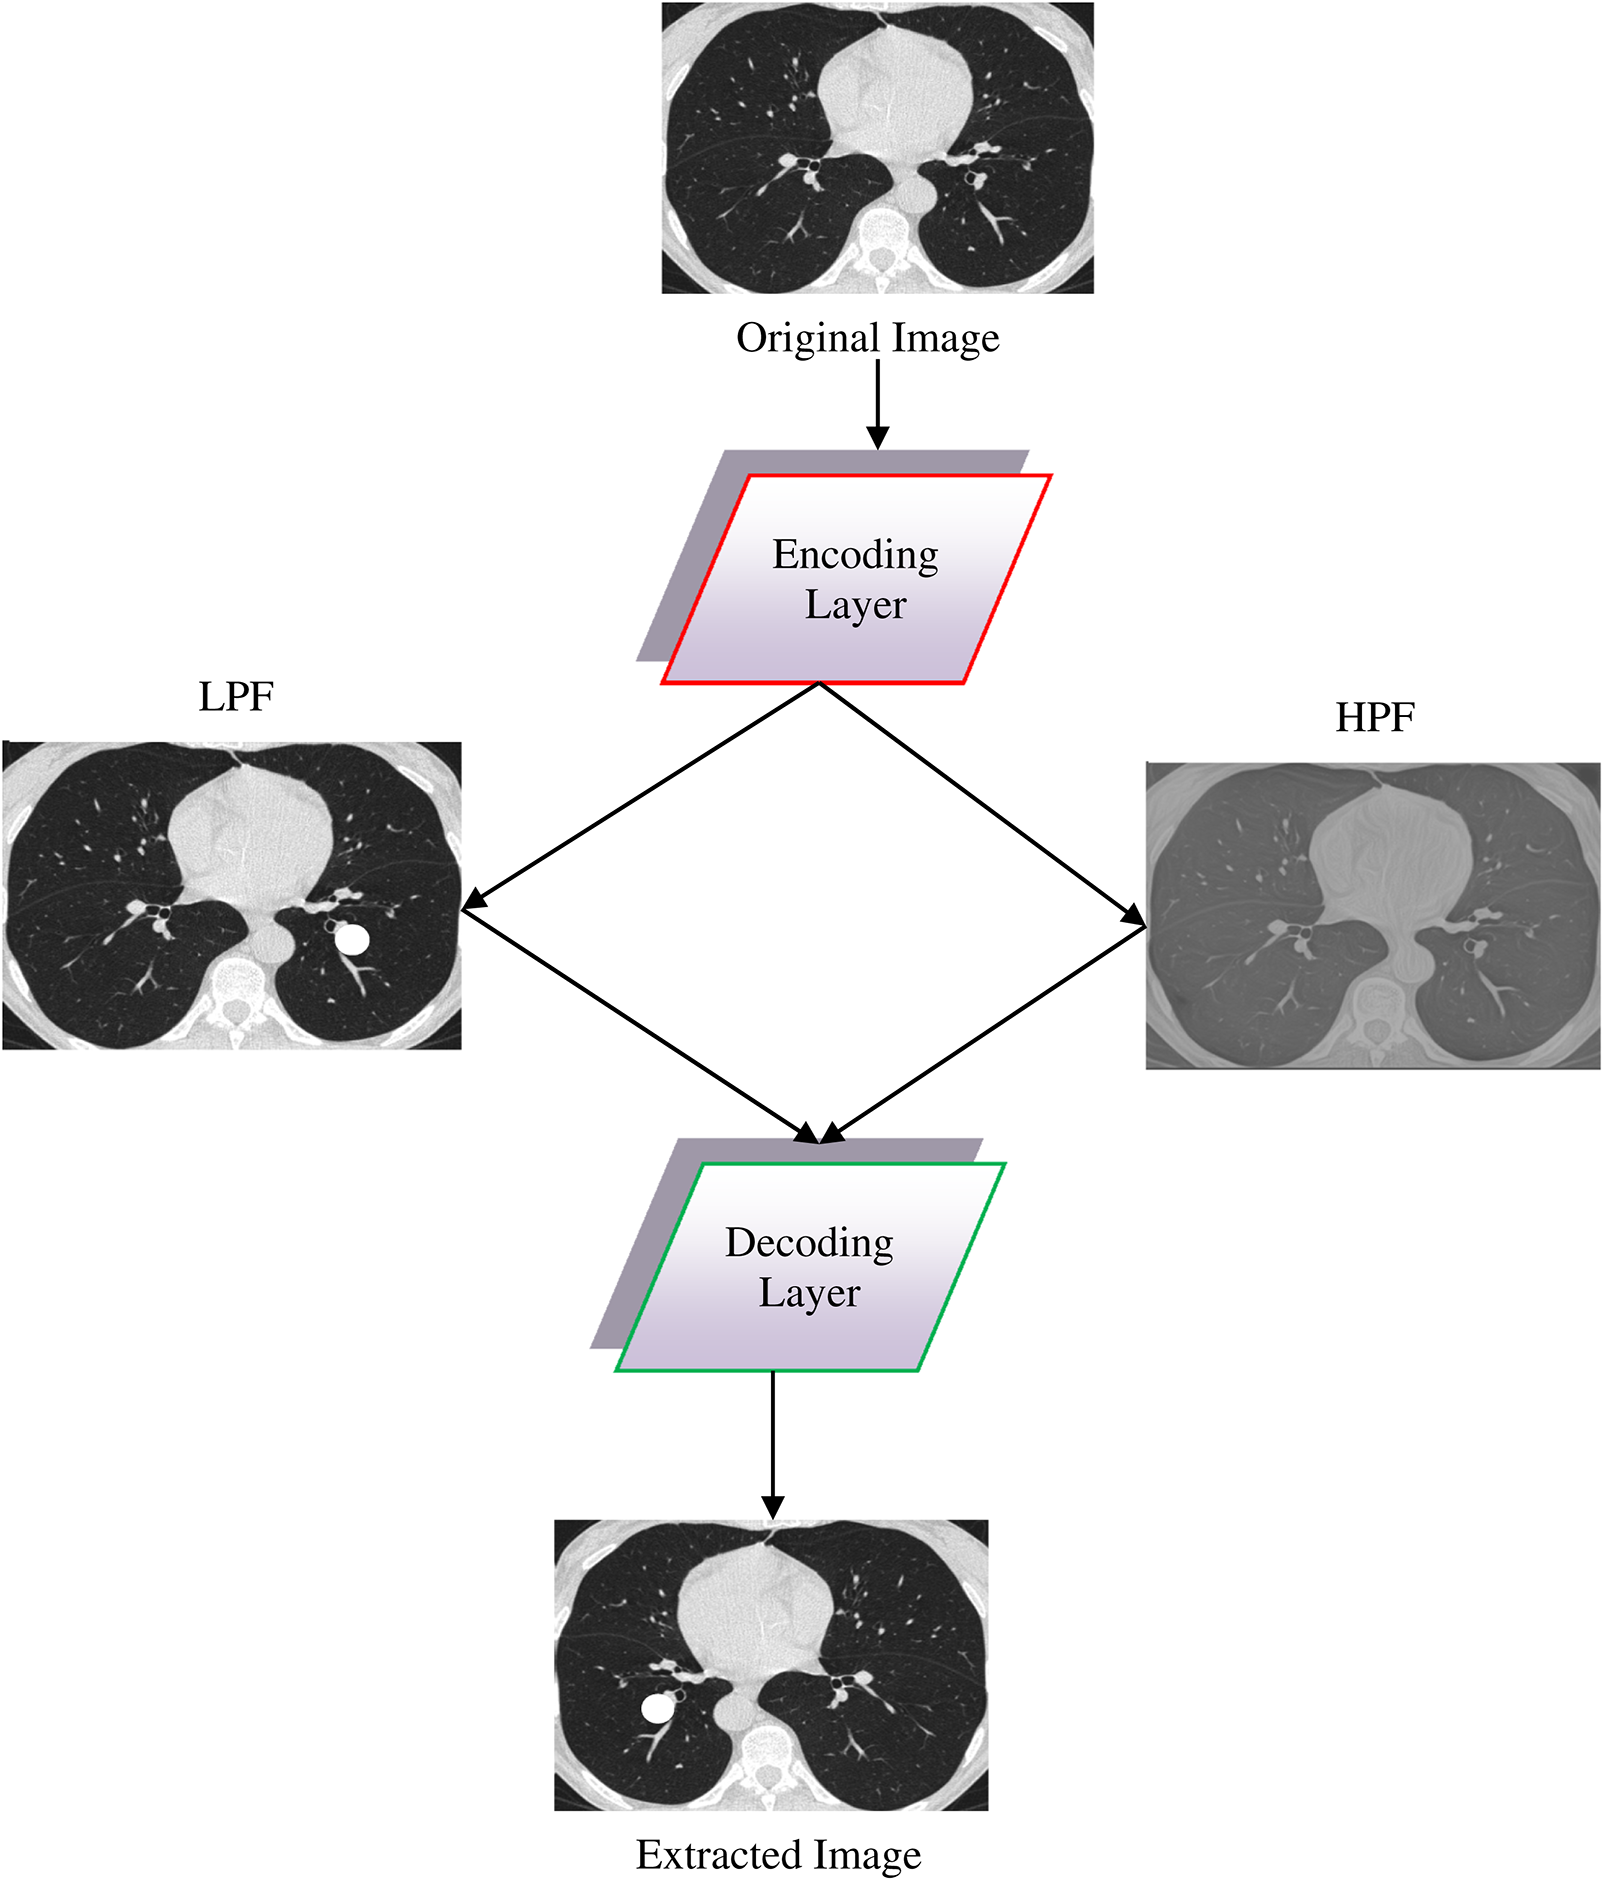

Fig. 3 presents the design of single-layer DWAE. This approach uses discrete wave transform using a Daubechies mother wavelet with class 2 to process the encoded image generated from the original image and produce estimation and precision coefficients through Low Pass Filter (LPF) and High Pass Filter (HPF). Using the DNN model, the approximation coefficients are further analyzed for classification. The presented architecture may be refined to create a more accurate replica.

Figure 3: Design for a single-layer DWAE